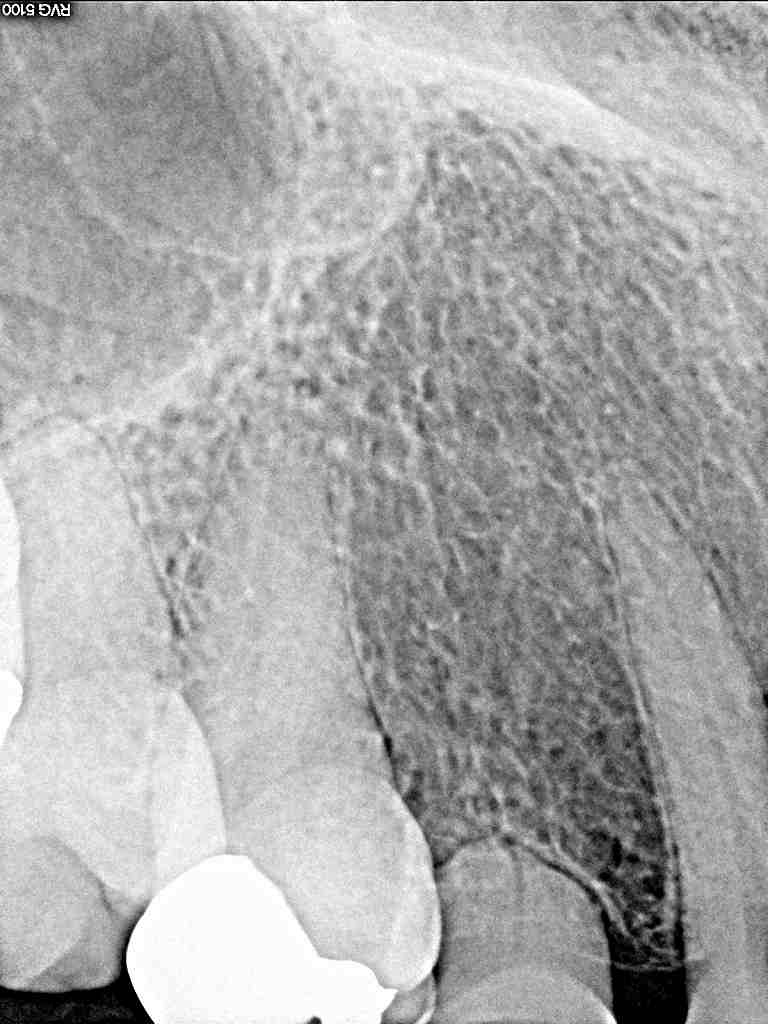

術前レントゲン